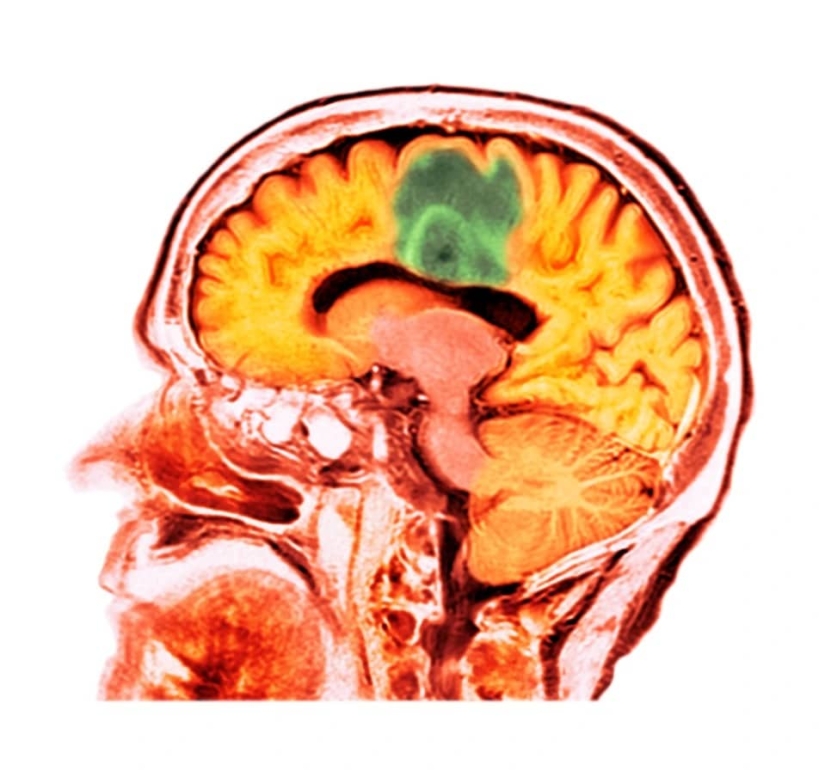

Brain cancer is one of the most severe forms of this disease, which is difficult to treat. But a group of scientists from Toronto found a way out using ultrasound beams. With their help, you can safely pass through the blood-brain barrier and ensure the flow of medicines.

This year, four women with breast cancer, whose metastases reached the brain, took part in the trials. They were treated with magnetic resonance focused ultrasound. Thanks to its waves, herceptin, an antibody—based drug, was delivered to the brain tissue. It was successfully absorbed by the body and contributed to the reduction of tumors without damaging healthy tissues.